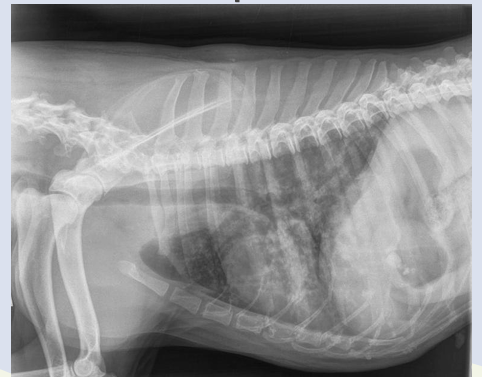

Interstitial pattern

aorta and vena cava is blurry